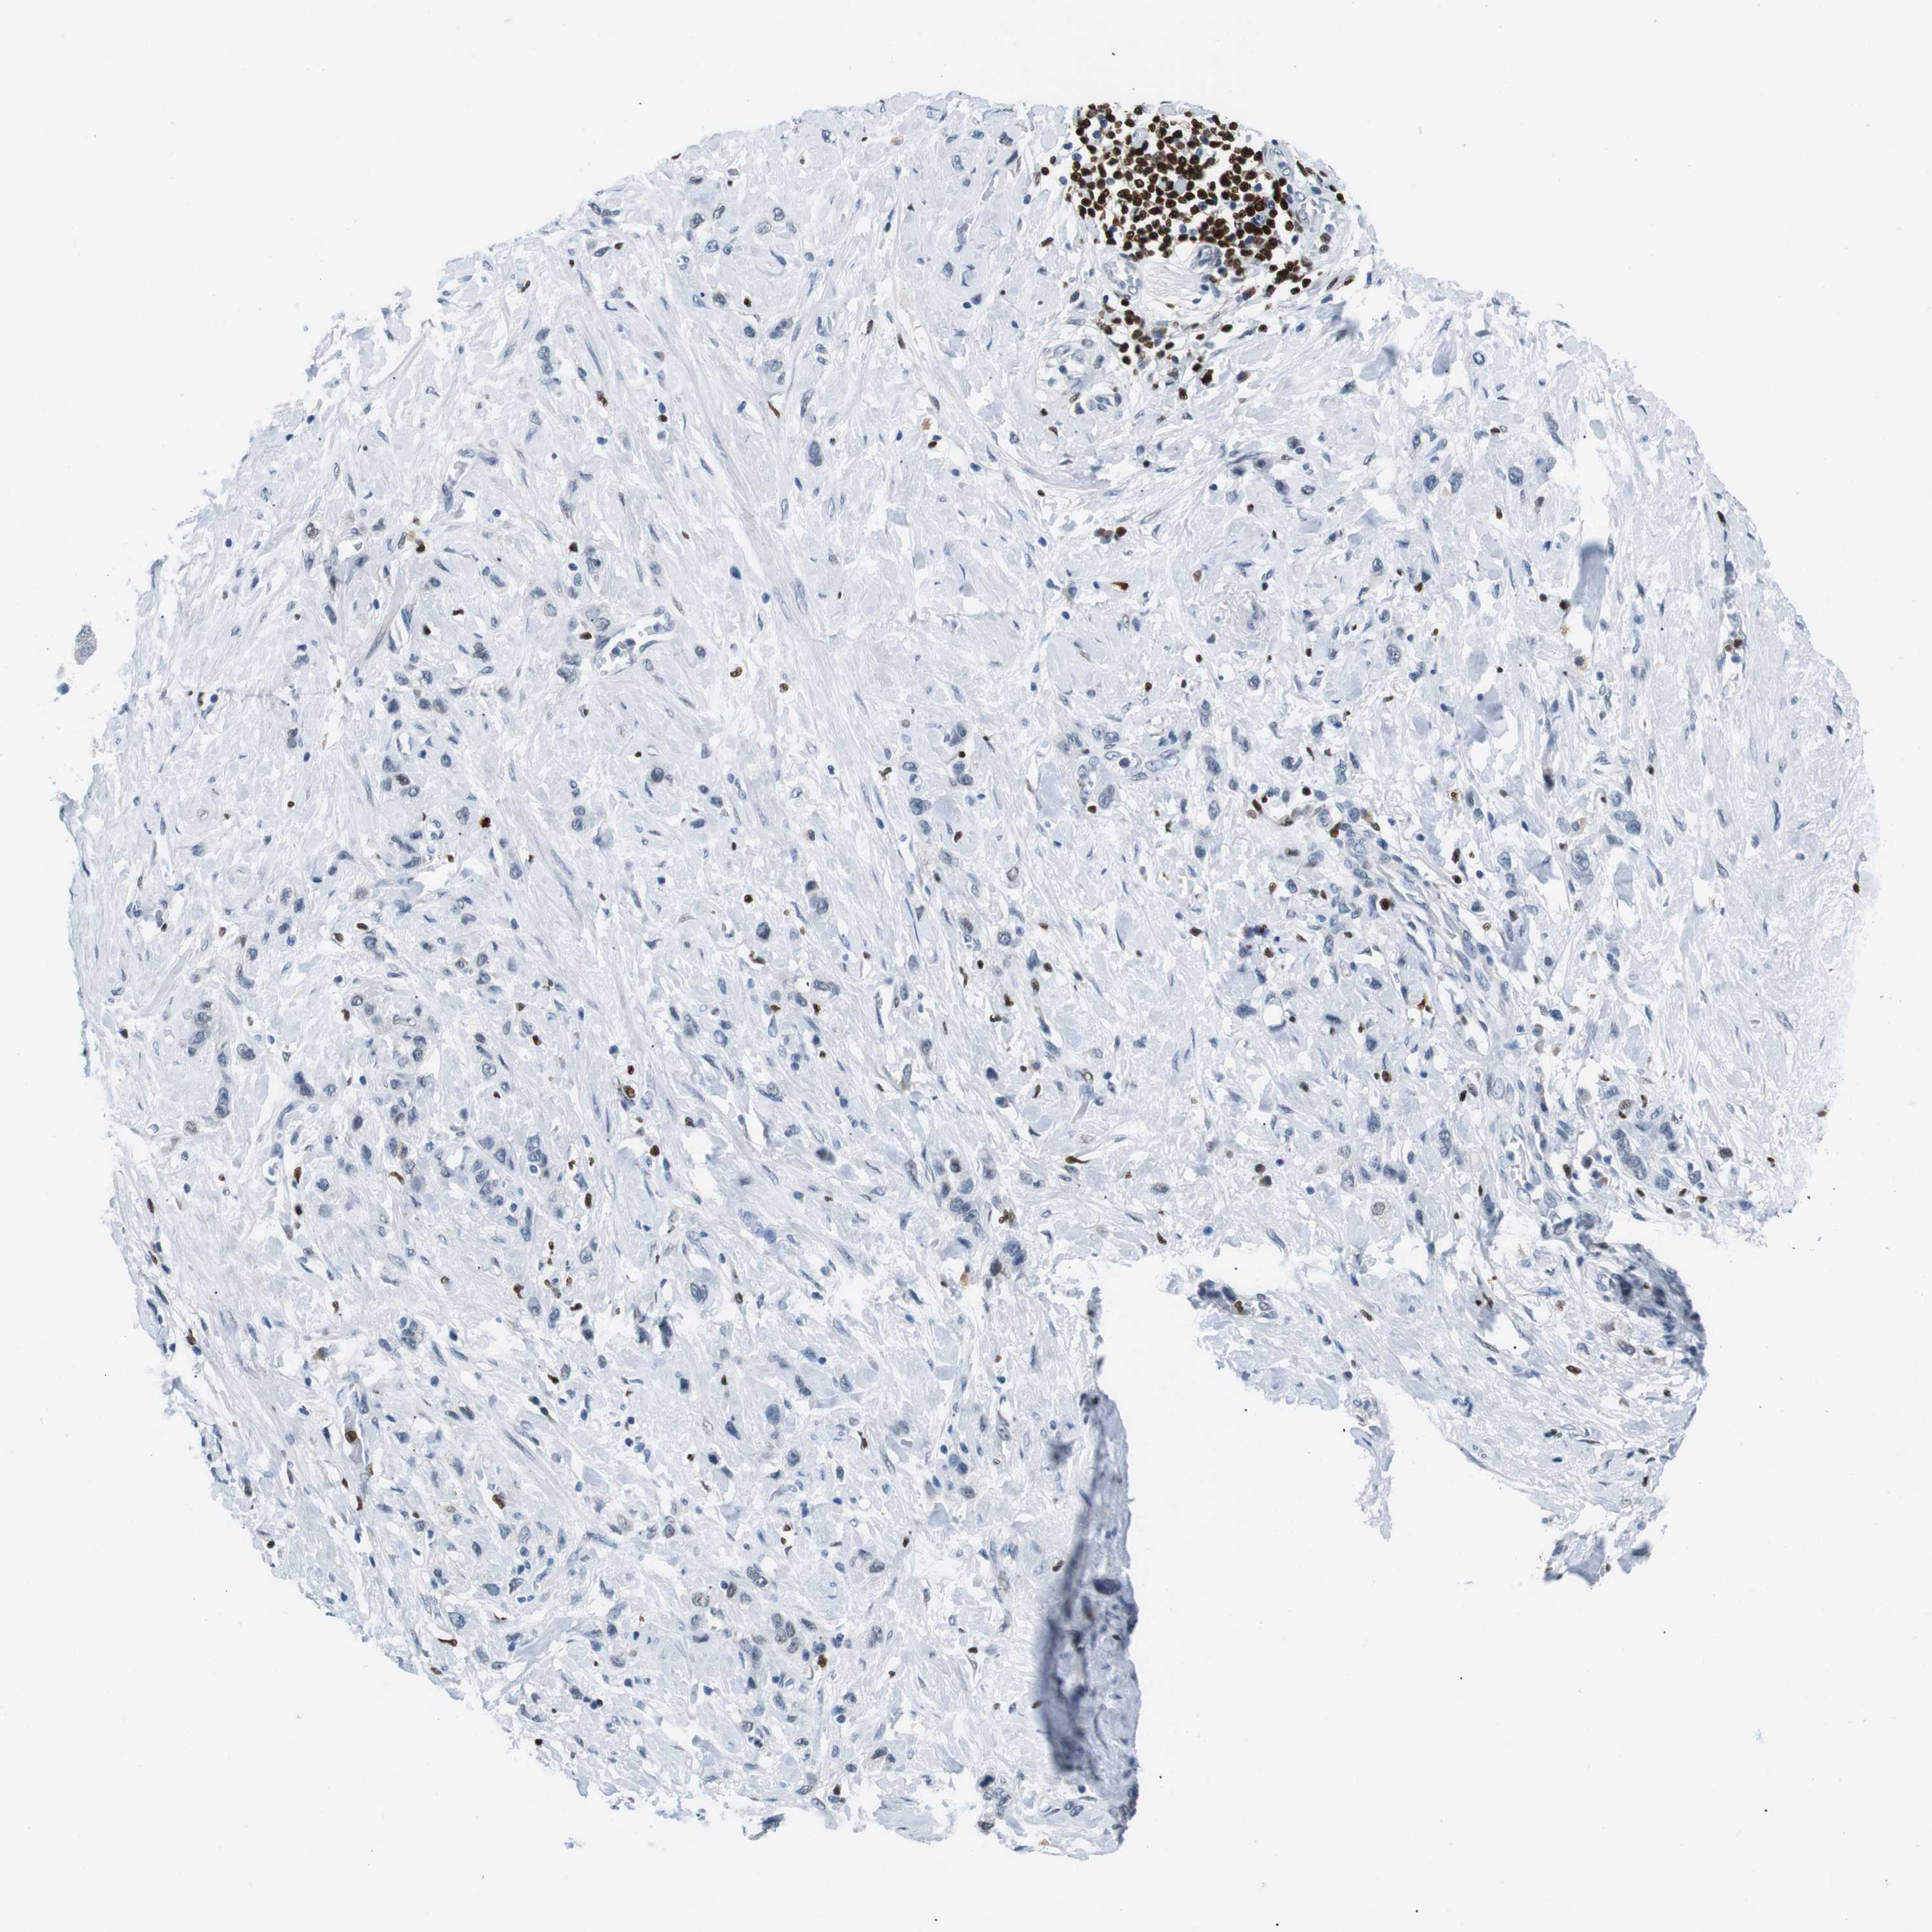

STOMACH CANCER - Protein expressioni

A mouse-over function shows sample information and annotation data. Click on an image to view it in a full screen mode. Samples can be filtered based on level of antibody staining by selecting one or several of the following categories: high, medium, low and not detected. The assay and annotation is described here.

Antibody stainingi

Antibody staining in the annotated cell types in the current human tissue is reported as not detected, low, medium, or high, based on conventional immunohistochemistry profiling in selected tissues. This score is based on the combination of the staining intensity and fraction of stained cells.

Each image is clickable and will lead to virtual microscopy that enables deeper exploration of all samples and also displays staining intensity scores, fraction scores and subcellular localization as well as patient and tissue information for each sample.

Antibody HPA002267

Antibody HPA002531

Antibody CAB013480

Staining

High

Medium

Low

Not detected

Intensity

Strong

Moderate

Weak

Negative

Quantity

>75%

75%-25%

<25%

None

Location

Nuclear

Cytoplasmic/membranous

Cytoplasmic/membranous,nuclear

Adenocarcinoma, NOS

Adenocarcinoma, High grade